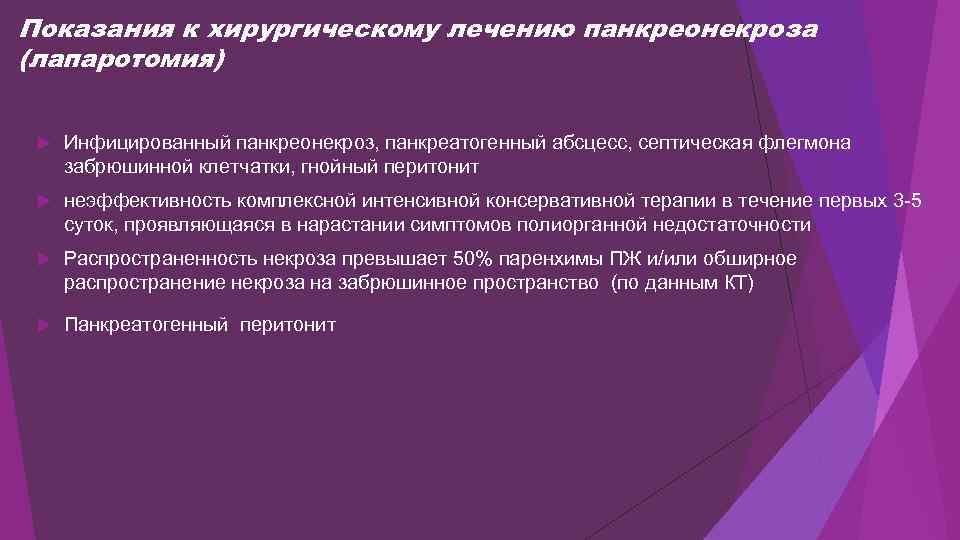

Показания к хирургическому лечению панкреонекроза (лапаротомия) Инфицированный панкреонекроз, панкреатогенный абсцесс, септическая флегмона забрюшинной клетчатки, гнойный перитонит неэффективность комплексной интенсивной консервативной терапии в течение первых 3 -5 суток, проявляющаяся в нарастании симптомов полиорганной недостаточности Распространенность некроза превышает 50% паренхимы ПЖ и/или обширное распространение некроза на забрюшинное пространство (по данным КТ) Панкреатогенный перитонит

Показания к хирургическому лечению панкреонекроза (лапаротомия) Инфицированный панкреонекроз, панкреатогенный абсцесс, септическая флегмона забрюшинной клетчатки, гнойный перитонит неэффективность комплексной интенсивной консервативной терапии в течение первых 3 -5 суток, проявляющаяся в нарастании симптомов полиорганной недостаточности Распространенность некроза превышает 50% паренхимы ПЖ и/или обширное распространение некроза на забрюшинное пространство (по данным КТ) Панкреатогенный перитонит